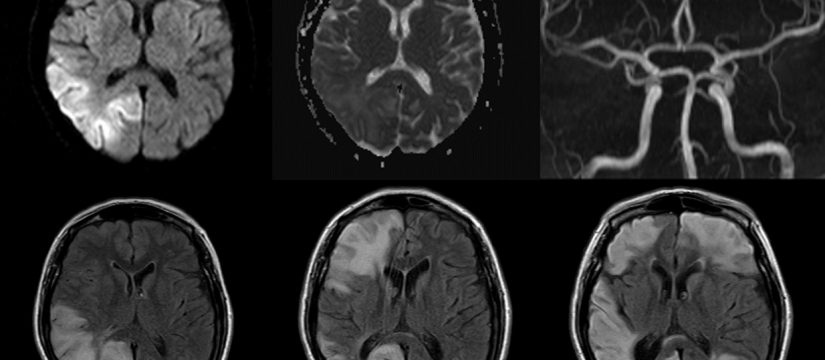

Varón de 40 años con esclerosis múltiple remitente-recurrente ya conocida, que consulta por disartria de varios días de evolución.